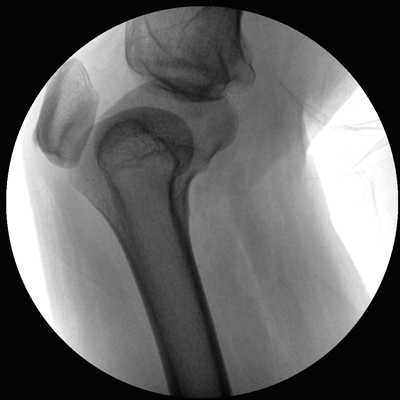

Clinical picture

臨床圖片